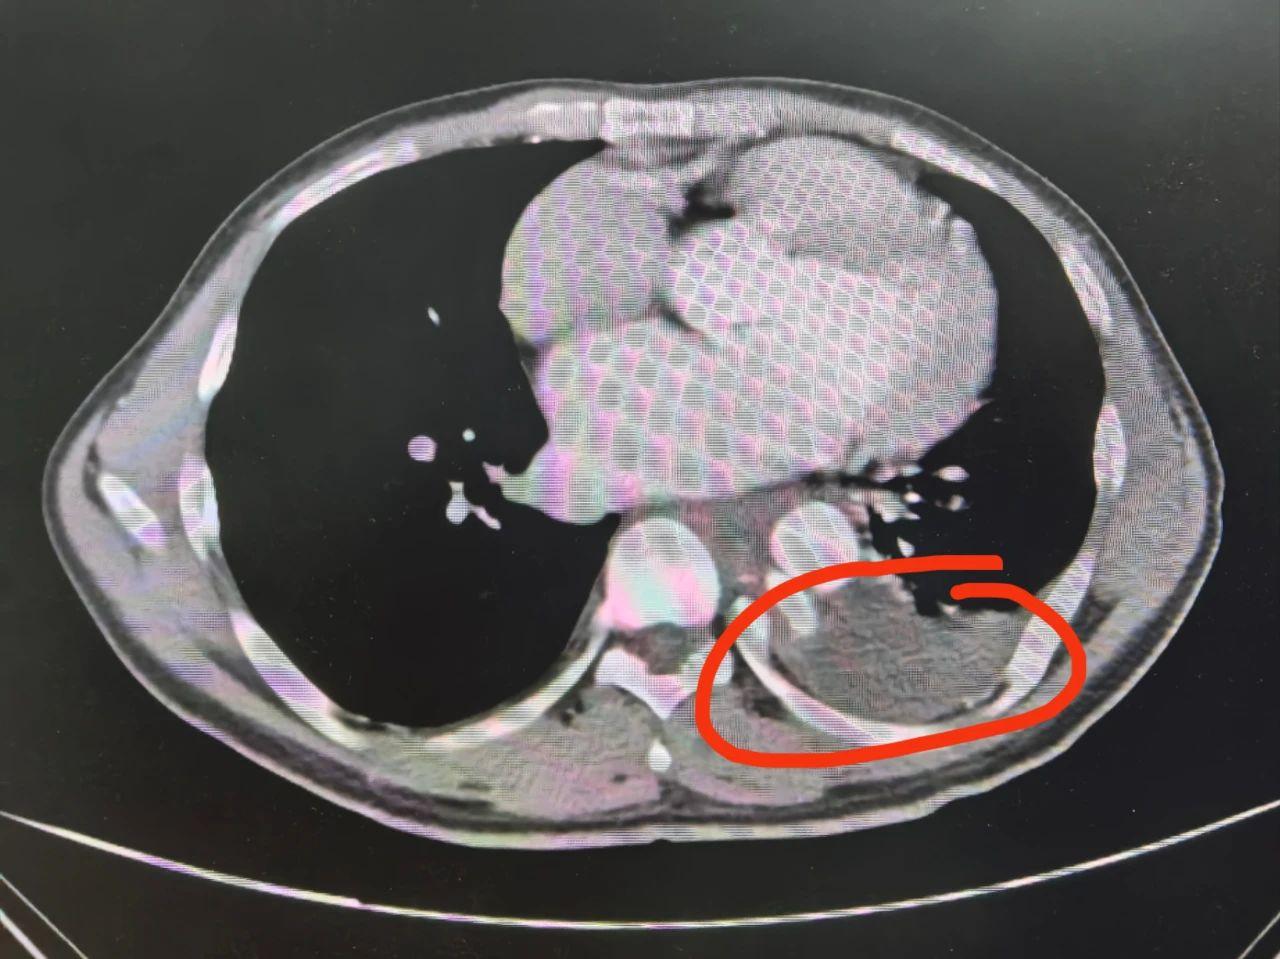

患者转入贵医大二院心胸外科后,医生对首次引出的600毫升血性积液产生怀疑,随即邀请介入科会诊。检查期间,患者胸腔再次引流出800毫升积液,进一步检查后,结果显示:胸主动脉破裂并伴假性动脉瘤形成,病情十分危急。介入科建议立即手术,通过“胸主动脉覆膜支架腔内隔绝术”稳定破裂血管区域,恢复正常血流。

血性胸腔积液